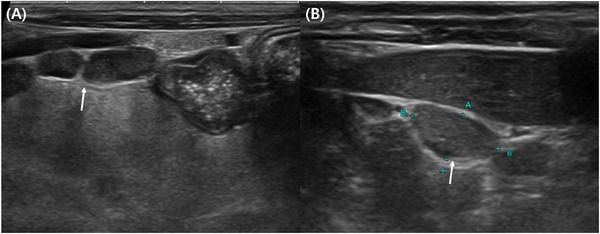

Case presentation: A 7-year-old castrated male Persian cat was referred due to generalized cutaneous nodules, including a prominent 4-5 cm nodule on the neck, and generalized lymphadenopathy. Neurological examination revealed an absent menace response in the left eye, raising suspicion of vision loss. Blood tests indicated hyperglobulinemia and the presence of medium-to-large lymphoid cells in the peripheral blood. Diagnostic imaging showed systemic lymphadenopathy, retinal detachment and minimal ascites. Fine needle aspiration of the lymph nodes revealed yeast-like organisms, and culture confirmed Cryptococcus neoformans. Initially treated with itraconazole, the therapy was switched to fluconazole due to better CNS penetration. The lymph node enlargement improved within one week, but further follow-up was limited due to owner constraints.